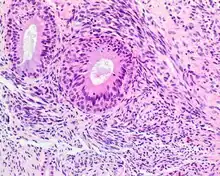

| A high-power view of a hematoxylin- and eosin-stained slide showing respiratory epithelial inclusions within a spindled cell neoplasm showing characteristics of a biphenotypic sinonasal sarcoma | |

- Infiltrative, highly cellular spindled cell neoplasm is poorly circumscribed and unencapsulated. Bone destruction or invasion is common. The cells show medium to long fascicles (nerve fibers), with a herringbone pattern. The cells are remarkably uniform with elongated nuclei. Delicate strands of intercellular collagen without ropy or dense deposition are seen. A very characteristic concurrent surface-type respiratory epithelial proliferation is found from the surface or in small cystic spaces around the cancer cells, often forming glands. The background may have a rich vascularity and usually has a small number of scattered lymphocytes. Extra growths or mitoses are rare, while necrosis, ulceration, and hemorrhage are usually absent.